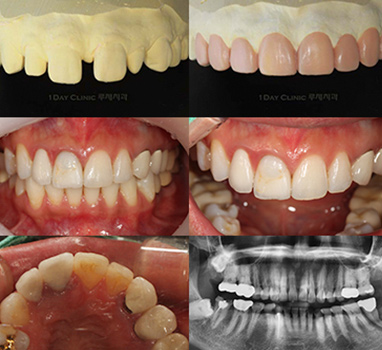

[하루 완성으로 시술 / 치료 당일 전, 후]